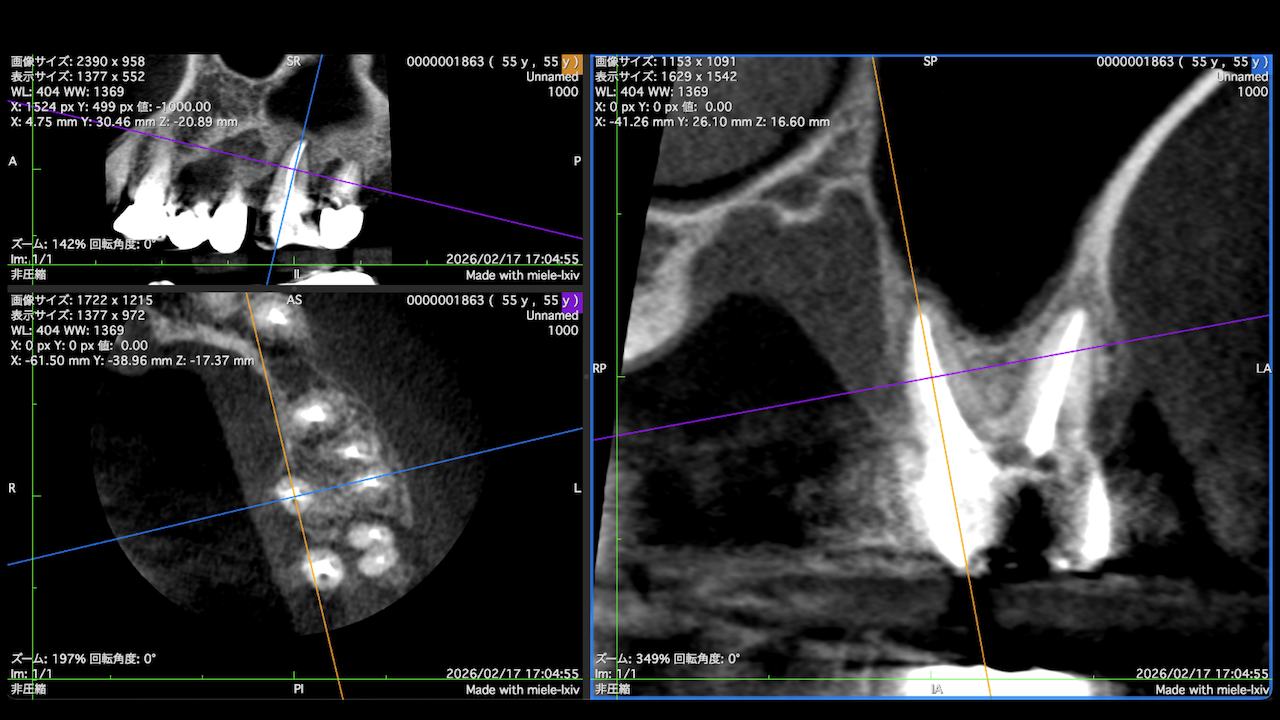

もう1ケースが以下だ。

#7がCold testに無反応である。

故に、#7,8の非外科的根管治療を行うことになった。

が、#8のメタルコアは外しにくいだろう。

CBCTでは2本とも口蓋側の皮質骨が消失している。

という絶望的な状況である。

ここから4ヶ月が経過すると…

臨床症状も皮質骨も大きく治癒している。

1年後の予後が気になるところであるが、すごくよくマネージメントできているだろう。